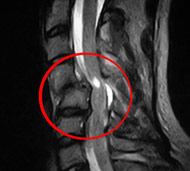

- Операція. Часто необхідно проведення термінової операції, щоб видалити фрагменти кісток, сторонні тіла, грижу міжхребцевого диска або зламані фрагменти хребця, що здавлюють вміст хребетного каналу. Операція також може знадобитися для стабілізації хребта, щоб запобігти появі болю або деформації. Існують деякі протиріччя щодо кращого часу проведення операції. Деякі хірурги вважають, що її необхідно виконувати раніше, інші вважають, що безпечніше почекати кілька днів до проведення будь-якої операції. Науково обгрунтованих доказів переваг ранніх (ургентних) операцій не отримано.

Зусилля нейрохірургів при лікуванні травм спинного мозку не мають вирішального впливу на прогноз патології. Навіть найбільш важкі операції з використанням найсучаснішого обладнання не завжди відновлюють втрачені функції. Зазвичай лікування дає позитивні результати, але діапазон може бути широким: від суб'єктивного поліпшення до повноцінного одужання. Операції підлягають 50% хворих, іншим доводиться лікуватися консервативно.

Мета операції - стабілізація хребта металевими конструкціями (імплантантами). Наша клініка була першою в СНД, яка застосувала сучасні конструкції при переломах хребта. Нині ми використовуємо імпортні конструкції типу CD Horison Legacy (США), Atlantis (США), Sextant (США), Socore (Франція). Операції вимагають складної рентгенівської техніки та спеціального інструментарію. При неускладнених переломах хребта хворі можуть ходити після таких операцій уже на другий - третій день. Також в Міжнародному центрі нейрохіургіі вперше в Україні впроваджено метод мініінвазивних операцій при переломах хребта.